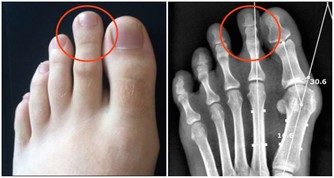

14. 下巴是腎和全身有酸痛的地方;也叫疲勞酸痛區。

15. 整個下巴到耳朵包括耳朵為腎區。